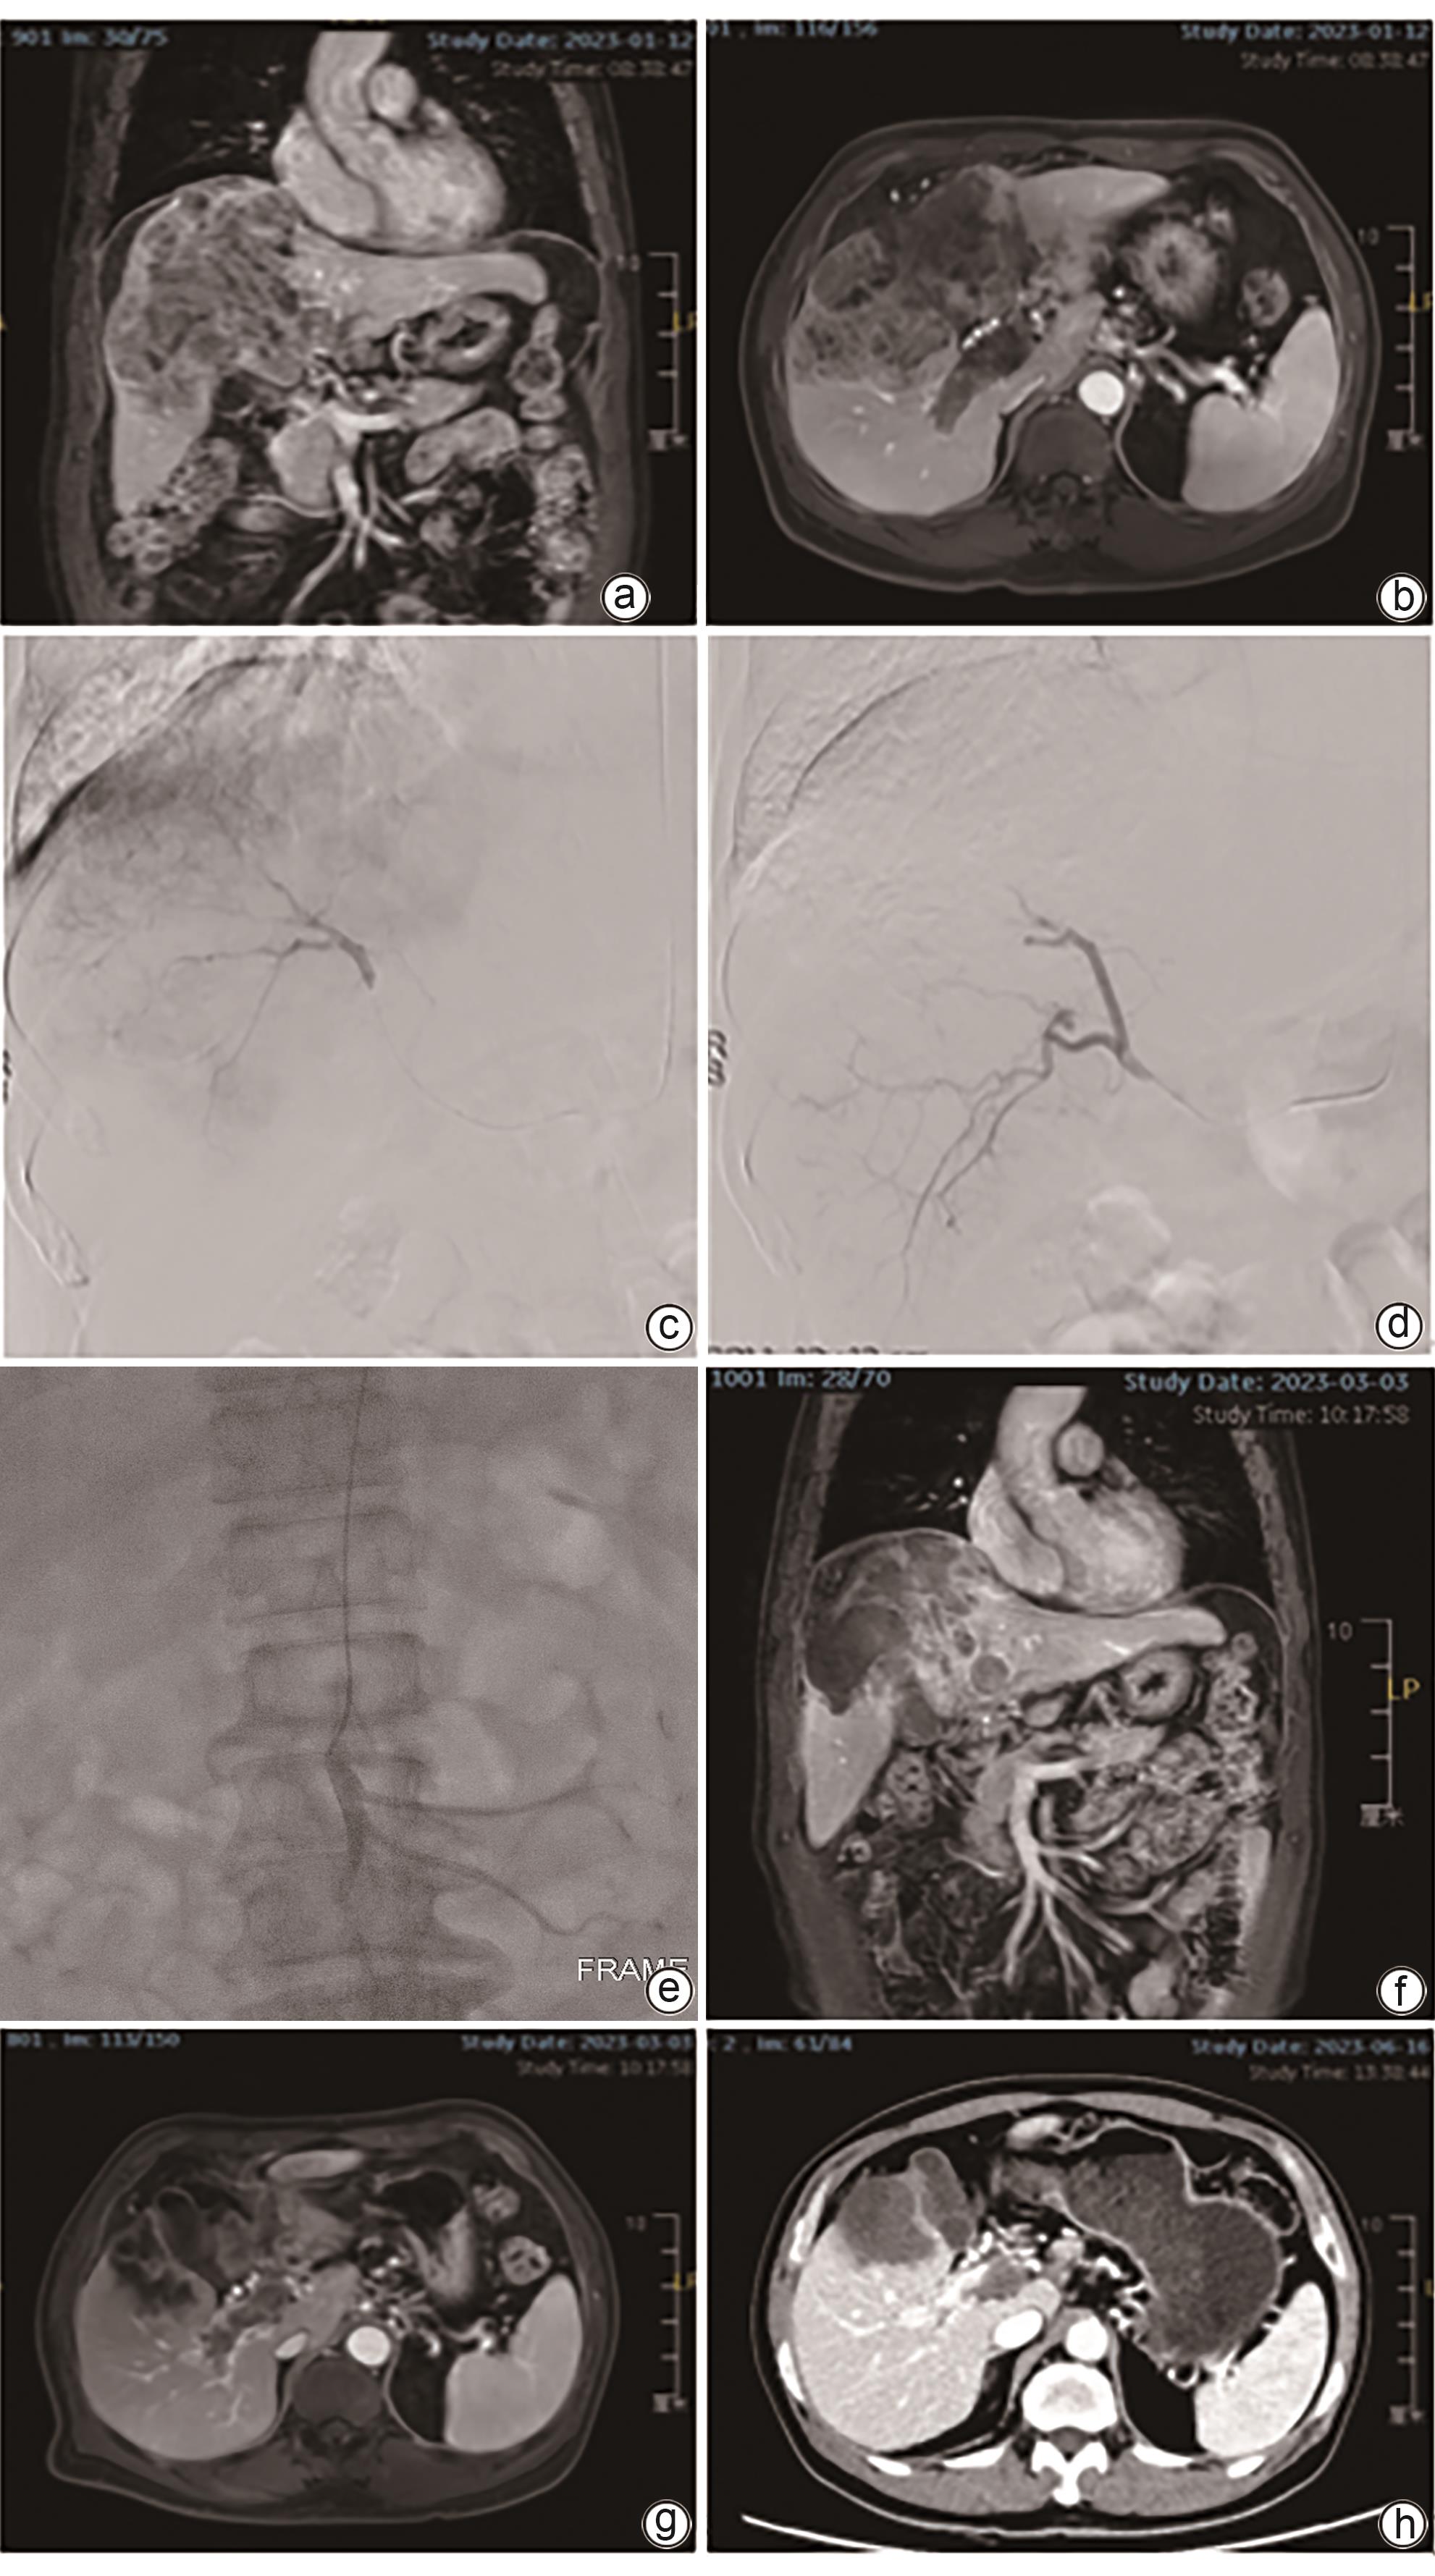

Efficacy of drug-eluting beads-transarterial chemoembolization combined with infusion chemotherapy via superior mesenteric artery in treatment of hepatocellular carcinoma complicated by portal vein tumor thrombus

Qianxin HUANG, Bin SHEN, Jinchang XIAO, Zhikang GAO, Duntao LYU, Yan LI, Hao XU, Qingqiao ZHANG

2024, 40(12): 2457-2463. DOI: 10.12449/JCH241216

Abstract(1496) HTML (336) PDF (1735KB)(70)

Abstract:

Objective  To investigate the efficacy of drug-eluting beads-transarterial chemoembolization (D-TACE) combined with infusion chemotherapy via superior mesenteric artery versus D-TACE alone in the treatment of hepatocellular carcinoma (HCC) complicated by portal vein tumor thrombus (PVTT).  Methods  A retrospective analysis was performed for the data of patients with HCC and PVTT who underwent interventional treatment in The Affiliated Hospital of Xuzhou Medical University from January 2022 to December 2023, among whom 15 patients received D-TACE combined with infusion chemotherapy via superior mesenteric artery and were enrolled as observation group, and after propensity score matching at a ratio of 1∶1, 15 patients who received D-TACE alone were enrolled as control group. Contrast-enhanced MRI of the upper abdomen was performed at 1, 2, and 3 months after surgery and every 3 months thereafter to evaluate the conditions of liver tumor and PVTT. Objective response rate (ORR) and disease control rate (DCR) were compared between the two groups. The independent-samples t test or the Mann-Whitney U test was used for comparison of continuous data between two groups, and the paired t-test or the Wilcoxon test was used for comparison of preoperative and postoperative data; the chi-square test was used for comparison of categorical data between two groups. The Kaplan-Meier curve was used to calculate the cumulative survival rate, and the Log-rank test was used for comparison between two groups.  Results  Both groups had a technical success rate of 100%, with no serious complications after surgery. The patients were followed up for 3-26 months (mean 10.5±6.7 months). At 3 months after surgery, there were no significant differences between the observation group and the control group in ORR (73.3% vs 53.3%, χ2=1.292, P=0.256) and DCR (93.3% vs 80.0%, χ2=1.154, P=0.283) for liver tumors, and compared with the control group, the observation group had significantly higher ORR and DCR for PVTT (ORR: 46.7% vs 13.3%, χ2=3.968, P=0.046; DCR: 100% vs 73.3%, χ2=4.615, P=0.032). The 3-, 6-, and 12-month cumulative progression-free survival rates were 93.3%, 86.2%, and 68.9%, respectively, for the observation group and were 80.0%, 62.2%, and 24.9%, respectively, for the control group (P=0.028), and the 3-, 6-, and 12-month cumulative overall survival rates were 100%, 88.9%, and 88.9%, respectively, for the observation group and were 93.3%, 85.6%, and 70.0%, respectively, for the control group (P=0.340).  Conclusion  Compared with D-TACE alone, D-TACE combined with infusion chemotherapy via the superior mesenteric artery shows better short-term efficacy in the treatment of HCC complicated by PVTT.